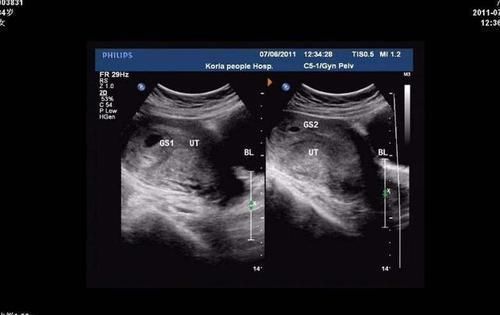

对于胎位不正来说,因为胎位一般是在孕34周的时候固定的,因此在34周的时候,一定要做一次产检,这次产检是判断孩子胎位正不正最关键的因素了。

通过这次产检及时发现孩子的胎位问题就可以避免在生产时因胎位不正导致的难产,减少孕妇和胎儿发生危险的概率。